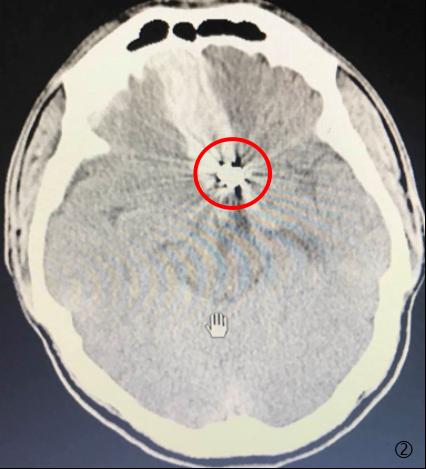

图1动脉瘤介入术后复发 图2动脉瘤术后复发并再次破裂出血

患者孙某,今年23岁,是个活泼开朗的阳光青年。三年前突发剧热头痛伴恶心呕吐急救至我们医院,查头部CT示“自发性蛛网膜下腔出血”,入院后查全脑血管造影DSA检查明确诊断为“前交通动脉瘤”,后因病情危急转至上海某三甲医院急诊行微创血管内弹簧圈栓塞术,术后恢复良好出院并叮嘱其3-6月左右需再次住院行全脑血管DSA检查,但患者一直未予以重视来医院复查,直至三年后又感有头痛不适,才想起来我院行全脑血管DSA检查,结果显示:右侧前交通动脉瘤瘤颈复发,大小约3.2mm×3.0mm×2.5mm,若不及时处理,随着时间的推移,复发动脉瘤也会越来越大,随时有再次破裂出血危及生命的可能。

目前,颅内动脉瘤的治疗方法主要有二种。一种是传统的手术治疗,这种治疗方式开展时间较长,疗效较为肯定,术后复发率也较低,但手术创面大且术后并发症多;另一种是血管内栓塞治疗,在其开展的20余年时间内,以创伤小和并发症少等优点迅速成为治疗颅内动脉瘤的一种重要方法。然而,无论是手术夹闭还是血管内弹簧圈栓塞,术后复发都是困扰神经外科医生的主要难题。既往研究表明,手术夹闭的复发率为4%-7%,年再出血发生率2%-4%,而动脉瘤栓塞术后的复发率为4.7%-33.6%,但术后残疾率低于手术治疗。一旦发现颅内动脉瘤有复发需要即时予以再次手术夹闭或栓塞进一步处理,只有在复发动脉瘤再次破裂发生前早发现、早诊断、早治疗,才能避免不可挽回的灾难发生。所以,颅内动脉瘤术后定期行全脑血造影(DSA)检查至关重要!